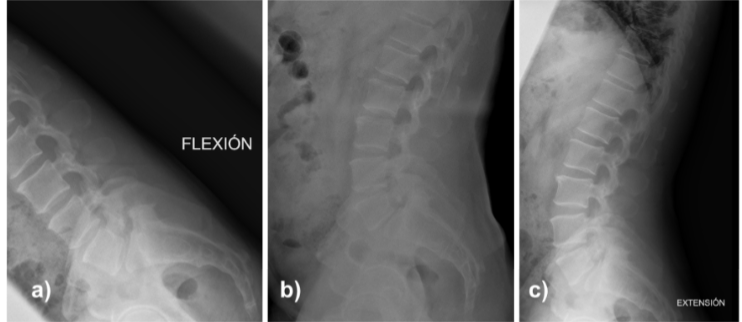

Figure 2: Dynamic lateral lumbar spine radiographs in flexion (a), neutral position (b), and extension (c).

Dynamic radiographs confirmed a stable grade I lytic anterolisthesis at L5–S1 and mild degenerative retrolisthesis at L4–L5 (Fig. 2). Full-spine standing radiographs showed pelvic incidence 70°, lumbar lordosis 68°, segmental lordosis L4–S1 42°, sacral slope 48°, thoracic kyphosis 45°, and sagittal vertical axis −12 mm, consistent with globally compensated sagittal alignment (Fig. 3).